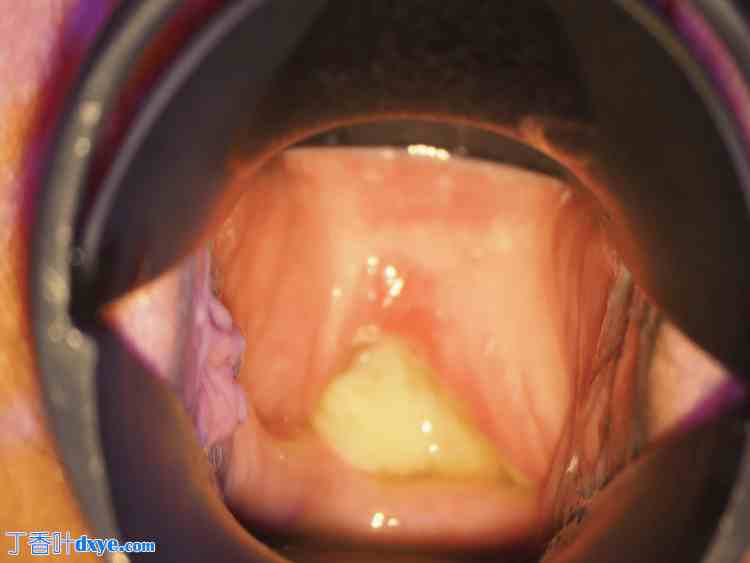

由于院仅有 2-0 号含抗生素的合成可吸收多股缝线,因此使用了这种缝线。患者术后恢复顺利,于术后第 8 天出院(图 10)。

图 10. 术后阴道镜检查结果。